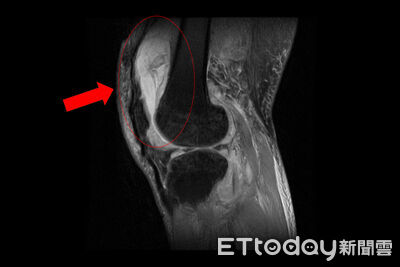

膝關節疼痛竟是「結核菌」引起!74歲賴先生長期左膝腫痛,以為是退化性關節炎,檢查抽取關節液發現非典型細菌感染,安排住院並多科會診,結果竟是「肺外結核感染」引起的骨結核病變。醫師指出,結核菌感染膝關節案例較為少見,因結核菌多半侵犯肺部,侵犯膝關節或脊椎的比例不到一成。 《詳全文...》